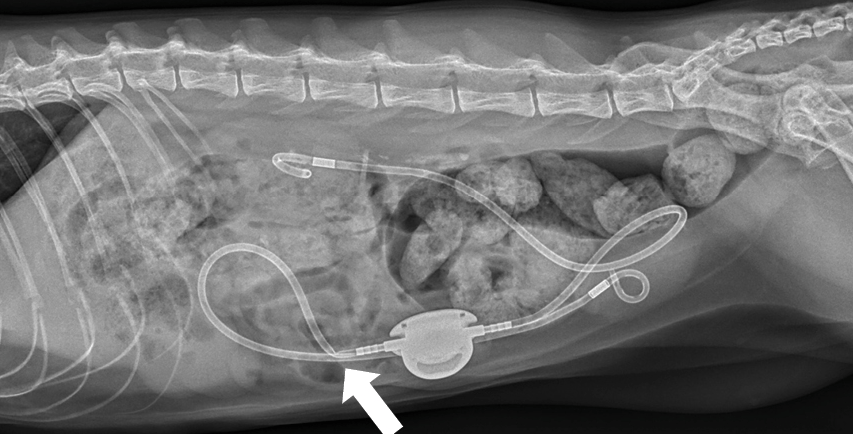

O SIDUS é um dispositivo médico veterinário indicado para desviar o fluxo da urina diretamente da bexiga para o exterior do organismo, contornando obstruções da uretra que não podem ser resolvidas por métodos convencionais.

O dispositivo cria uma nova via de eliminação da urina, conectando a bexiga a um reservatório subcutâneo, por meio de um sistema de cateteres.